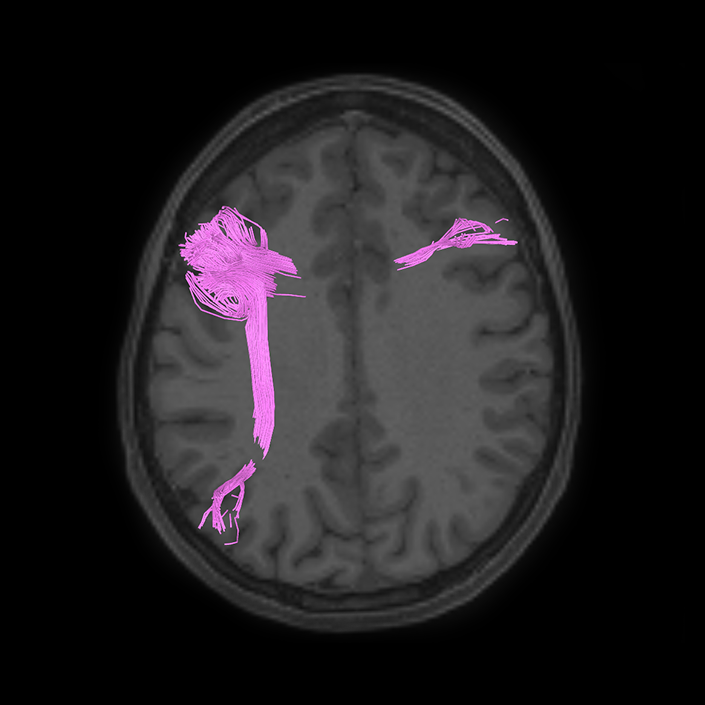

ᐅ SummaryArea SFL: part of the supplementary motor regions. Known to be hemispherically asymmetric. Specifically, the left hemisphere shows more activity when listening to stories and when a participant is matching objects based on a verbal cue. Compared to area 8BL, area SFL shows more activation when listening to a story, matching objects based on verbal cues and in social interaction settings. Compared to area s6-8, area SFL shows more activation in the left hemisphere when individuals listen to a story. In the right hemisphere, area SFL is activated insocial interaction settings and is deactivated during object feature comparison tasks. ᐅ Where is it?Area SFL (superior frontal language area) is located on the posterior medial SFG straddling over the interhemispheric cleft. ᐅ What are its borders?Area SFL borders SCEF inferiorly. Its anterior inferior neighbor is area 8BM and its anterior superior neighbor is area 8BL. Areas 6ma and s6-8 are its lateral neighbors. ᐅ What are its functional connections?Area SFL demonstrates functional connectivity to areas 8BL, 8AV, 9a, 9p, and 9m in dorsolateral frontal lobe, areas 8BM, d32, areas 44, 45, 47L, and 47s in the inferior frontal lobe, area 55b in the premotor areas, areas STSda, STSdp, STSva, STSvp, TE1a, and TGd in the temporal lobe, area PGi in the lateral parietal lobe, and areas 31pv, and 31pv in the medial parietal lobe. ᐅ What are its white matter connections?Area SFL is structurally connected to pyramidal tracts, the frontal aslant tract and contralateral hemisphere. Connections to pyramidal tracts descend through the posterior limb of the internal capsule and cerebral peduncle to the brainstem. The FAT connects SFL with the inferior frontal gyrus, terminating at parcellations 44, IFSp and MI. Contralateral connections course through the body of the corpus callosum to SCEF and 8BL. Local short association fibers connect with SCEF, 8BL, SFL and 6ma. ᐅ What is known about its function?Area SFL was subdivided from adjacent parcellations due to differences in myelin thickness and functional activity. Area SFL is known to be hemispherically asymmetric. Specifically, the left hemisphere shows more activity when listening to stories and when a participant is matching objects based on a verbal cue. Compared to area 8BL, area SFL shows more activation when listening to a story, matching objects based on verbal cues and in social interaction settings. Compared to area s6-8, area SFL shows more activation in the left hemisphere when individuals listen to a story. In the right hemisphere, area SFL is activated in social interaction settings and is deactivated during object feature comparison tasks. |

A: lateral-medial

B: anterior-posterior

C: superior-inferior

DTI image |